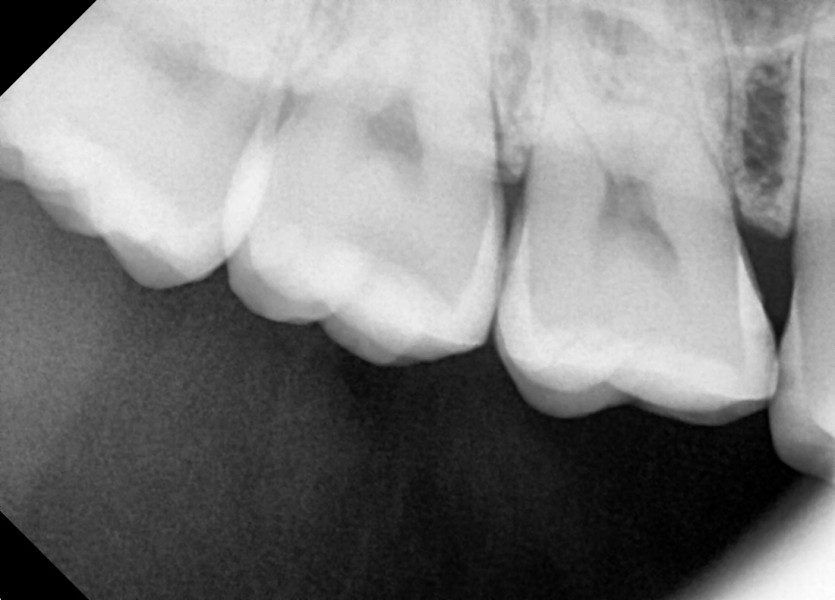

#18,48 사랑니 발치

구강 외과 전문의가 당일 발치했습니다.